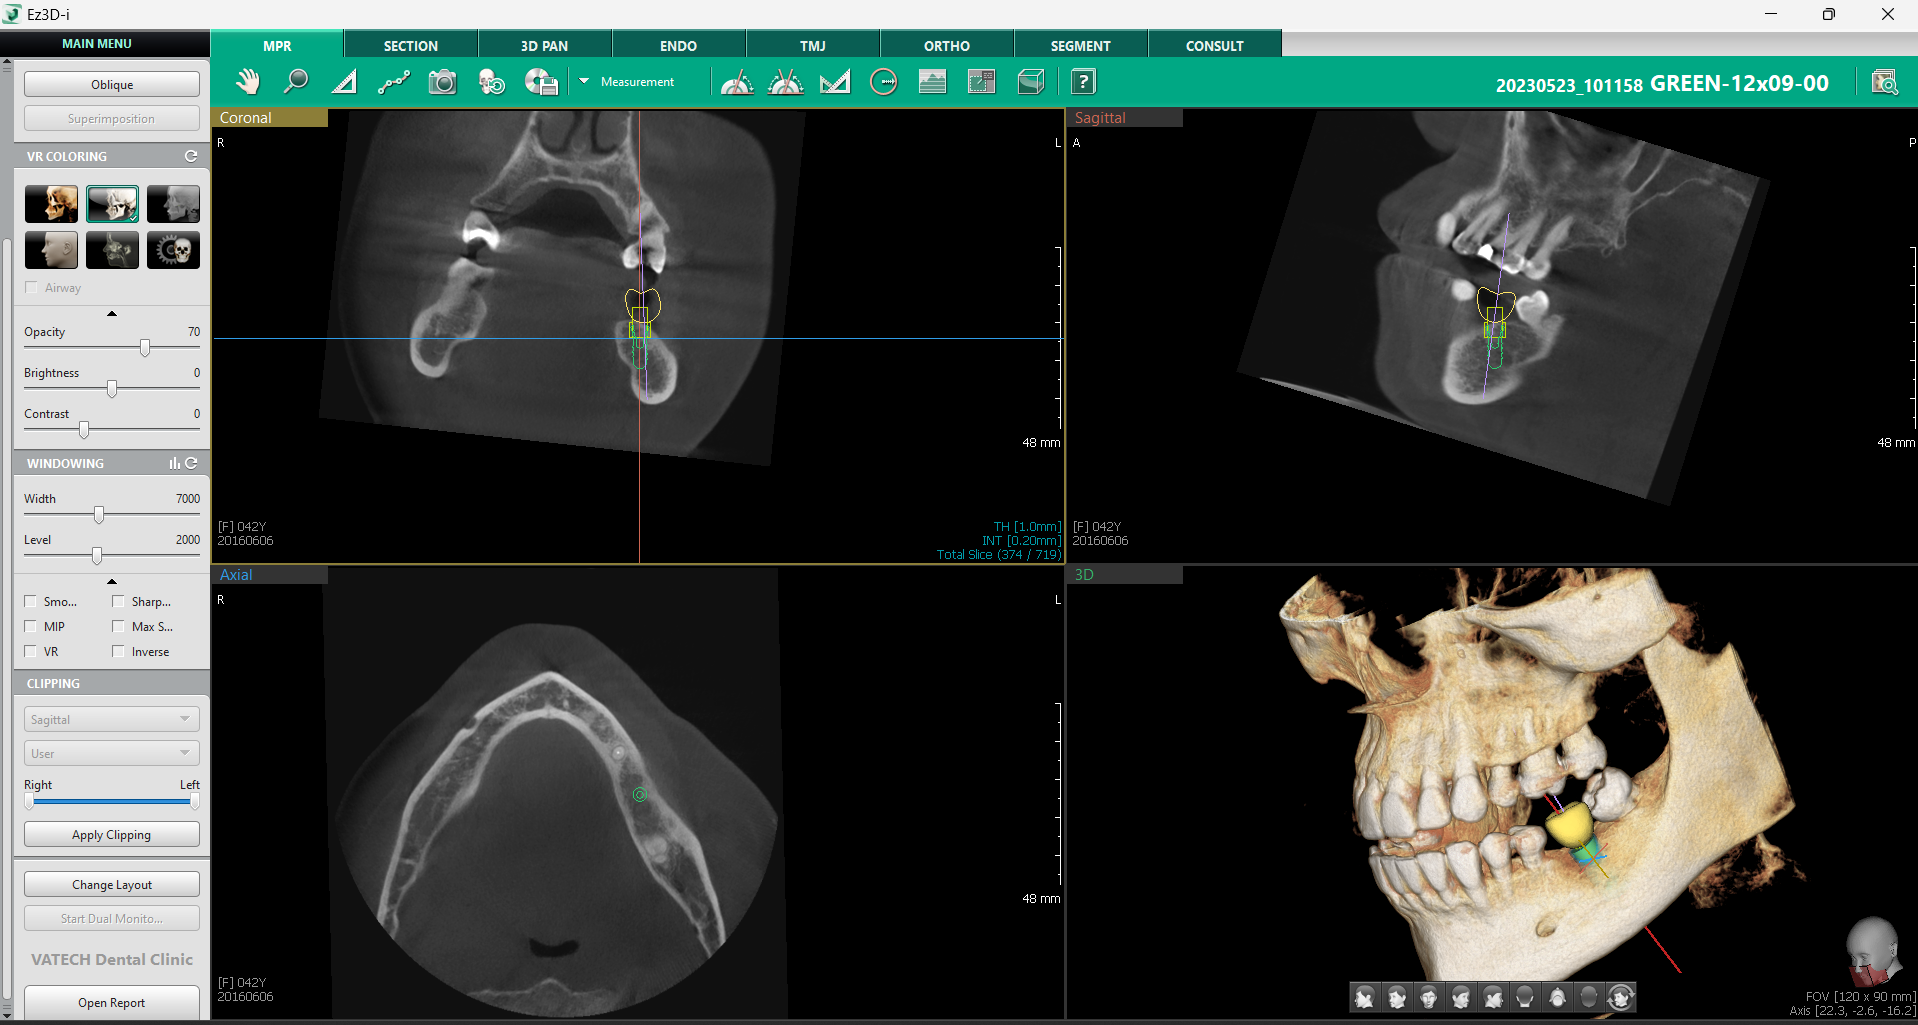

a. Setarea axei MPR

Funcția Set MPR Axis este un instrument esențial pentru verificarea poziționării corecte a implantului, oferind o metodă rapidă și eficientă de analiză a sănătății osoase și a plasării implantului în raport cu structurile adiacente.

Printr-un simplu click dreapta pe implant și selectarea opțiunii „Set MPR Axis” din fila MPR, software-ul realiniază automat toate planurile imagistice conform poziției implantului. Această funcție oferă medicului o perspectivă detaliată asupra implantului în raport cu densitatea osoasă și permite ajustarea rapidă a poziției înainte de finalizarea procedurii.